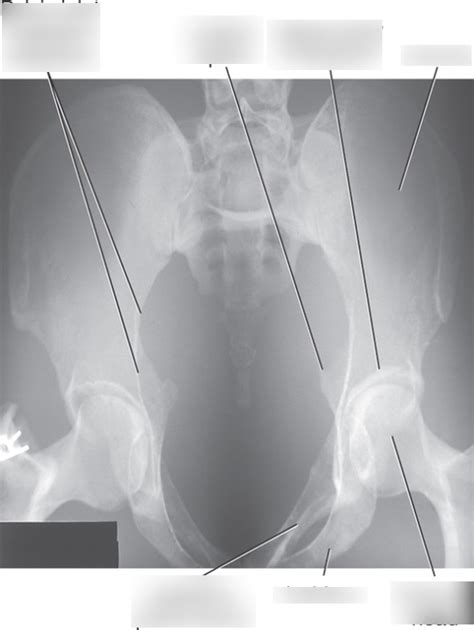

Key Anatomical Structures to Identify:

• Sacroiliac (SI) Joints: These joints connect the sacrum to the iliac bones. On the AP Axial view, you should be able to clearly visualize the SI joints and assess their alignment and joint space.

• Symphysis Pubis: This is the joint where the two pubic bones meet in the front of the pelvis. Look for any widening or displacement of the symphysis pubis, which could indicate a pelvic fracture or instability.

• Pelvic Inlet: This is the opening into the true pelvis. The AP Axial view is designed to provide a clear view of the pelvic inlet, allowing you to assess its shape and symmetry. Any distortion or asymmetry could suggest a fracture or dislocation.

• Iliac Crests, Ischial Spines, and Pubic Rami: These bony landmarks should be clearly visible and free from any obvious fractures or deformities.

• Sacrum and Coccyx: Although the primary focus is on the pelvic ring, it’s also important to assess the sacrum and coccyx for any abnormalities.

• Rotation: Check for rotation by assessing the symmetry of the obturator foramina and the iliac wings. If one obturator foramen appears larger than the other, or if one iliac wing is more prominent, the pelvis is likely rotated.